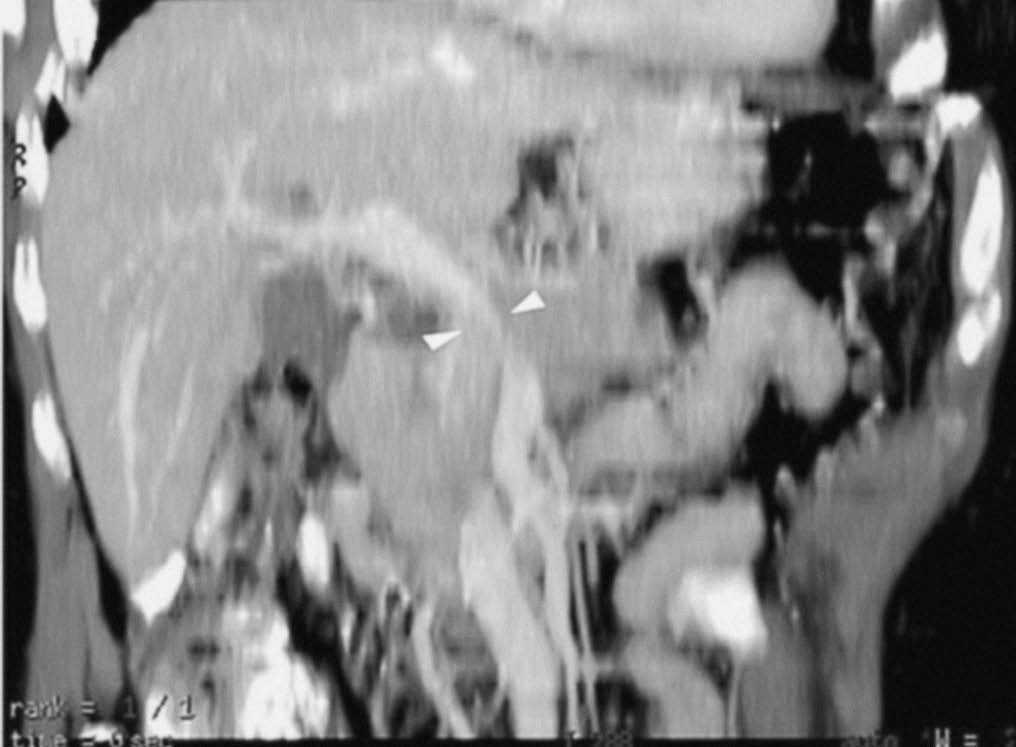

Fig. 3.--Estudio de tomografía computarizada con contraste endovenoso en fase venosa portal en un paciente con neoplasia de páncreas. Masa heterogénea mal definida en el cuerpo pancreático. (A) Sección axial que no permite identificar el eje esplénico-mesentérico-portal. (B) La reconstrucción multiplanar oblicua coronal, orientada en el plano del confluente venoso demuestra de forma clara la disminución del calibre de la vena porta en su origen y de la vena mesentérica superior en su confluencia con la vena porta (puntas de flecha), que permite establecer el diagnóstico de infiltración venosa local, mostrando la longitud del segmento venoso afectado.

La TC helicoidal permitió, además, llevar a cabo un estudio detallado de los pequeños vasos arteriales y venosos peripancreáticos24-26 (fig. 2), mostrando mejores resultados que la angiografía por sustracción digital en el diagnóstico de la invasión vascular por cáncer de páncreas27. La valoración de estas pequeñas estructuras vasculares mejora el rendimiento de la TC en la estadificación tumoral28,29. La posibilidad de reconstruir en diferentes planos del espacio las imágenes axiales obtenidas ha sido evaluada por algunos autores30,31, obteniendo un mayor rendimiento de la TC para determinar la invasión vascular, fundamentalmente venosa, cuando las secciones transversas se interpretan en combinación con las reconstrucciones multiplanares que cuando se interpretan únicamente las secciones transversas (92-96% frente a 69-70%) (fig. 3).